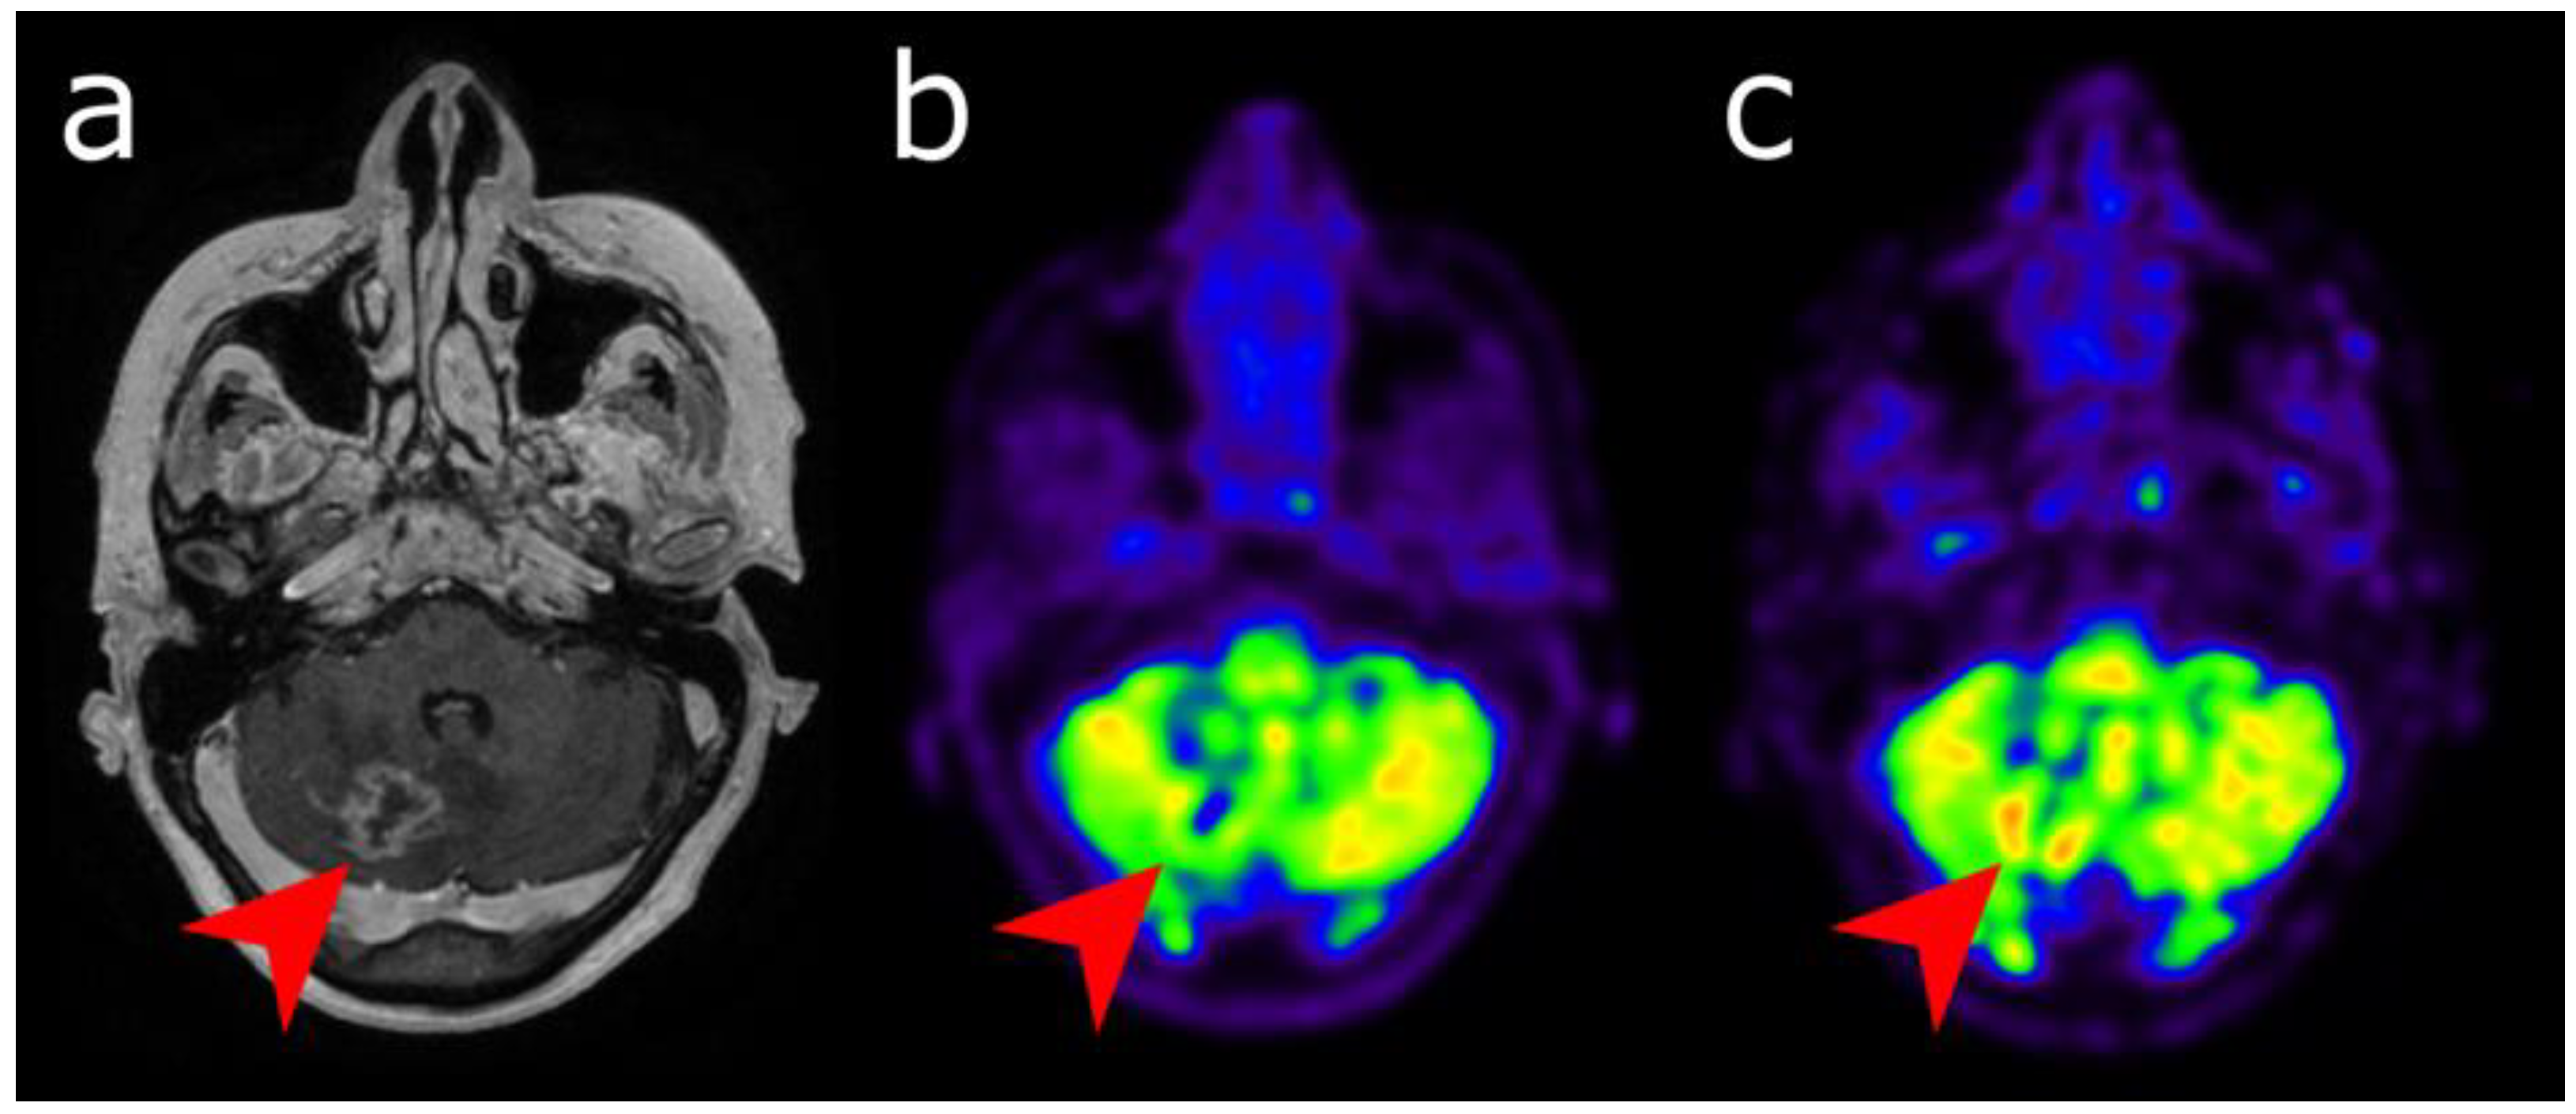

5. Meningioma

5.1. Diagnostic and Characterization

5.2. Defining Tumor Extent